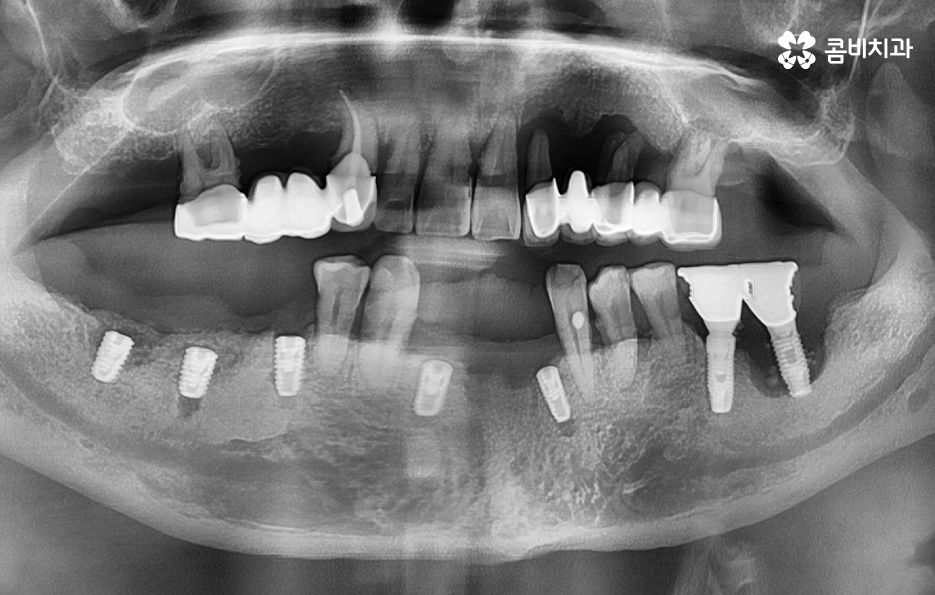

위 환자분의 케이스는 치주염이 심해져서 치아를 잃게 되기도 했지만 윗니의 경우 브릿지로 치아 기능을 유지하다가 결국 임플란트를 하게 된 사례로 볼 수 있어요

과거에는 임플란트 치료 자체가 없어서 브릿지나 틀니와 같은 치료를 할 수 밖에 없었지만 브릿지와 틀니의 한계점은 치아의 기능적인 부분에서도 한계점이 분명하지만 그에 더해 치조골이 점점 내려 앉고 흡수된다는 점에서도 임플란트의 장점이 명확하다고 할 거예요